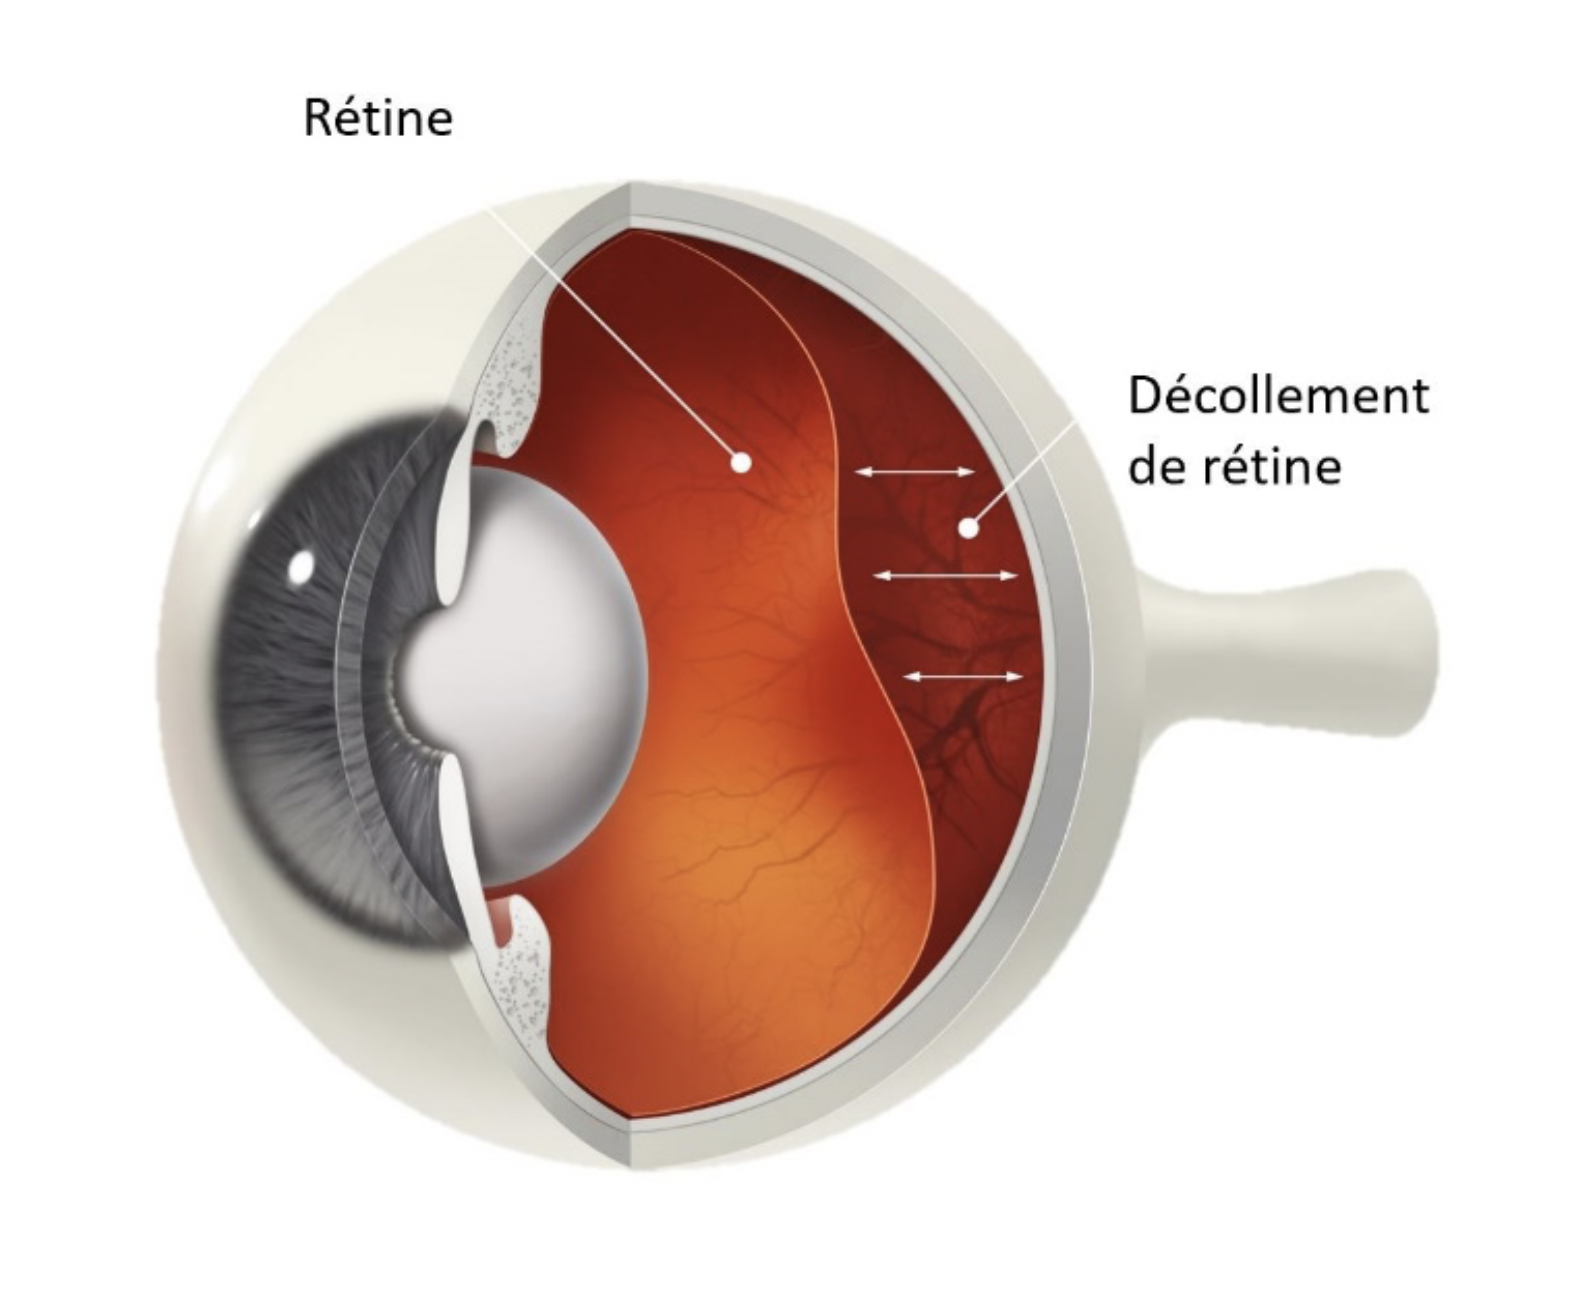

decollement retine photo Décollement de rétine

If you are searching about Décollement postérieur du vitré (DPV) | Institut de la rétine | CHU de you’ve visit to the right page. We have 35 Pictures about Décollement postérieur du vitré (DPV) | Institut de la rétine | CHU de like Le décollement de rétine - Pour la vision | Association CRO, Fond d’oeil_Décollement rétine supérieur avec déchirure rétinienne and also Décollement de rétine - Ophtalmologie l’Union. Read more: